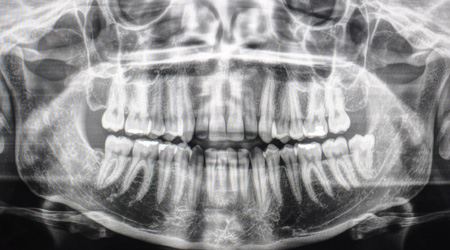

La panoramica dentale è un esame radiografico molto utilizzato in campo odontoiatrico in quanto permette di studiare sia l’arcata superiore che l’arata dentale inferiore. Il nome specifico della panoramica è Ortopantomografia, questa radiografia viene eseguita con un’apparecchiatura chiamata ortopantomografo.

La panoramica serve per esegurire uno studio globale delle arcate dentale e delle ossa mascellari (mandibola e macellare superiore), inoltre serve per valutare anche l’articolazione temporo mandibolare.Le indicazioni principali alla panoramica sono: